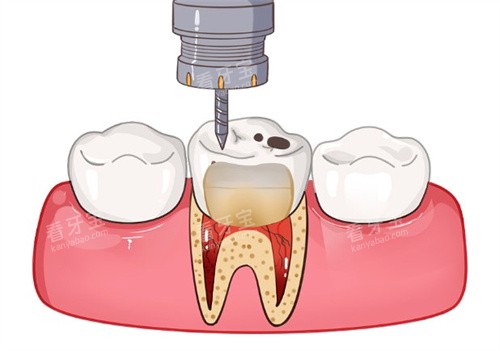

第二步是清除感染组织和根管预备。医生会用细小的器械把牙髓腔里感染的神经、血管全部清除掉,然后反复冲洗根管内部,把残留的感染物质清理干净。之后会对根管进行扩大和修整,让根管变得更规则,为后续的填充做准备。这一步过程中,大家可能会感觉到器械在牙齿里操作的震动感,但不会有明显疼痛。